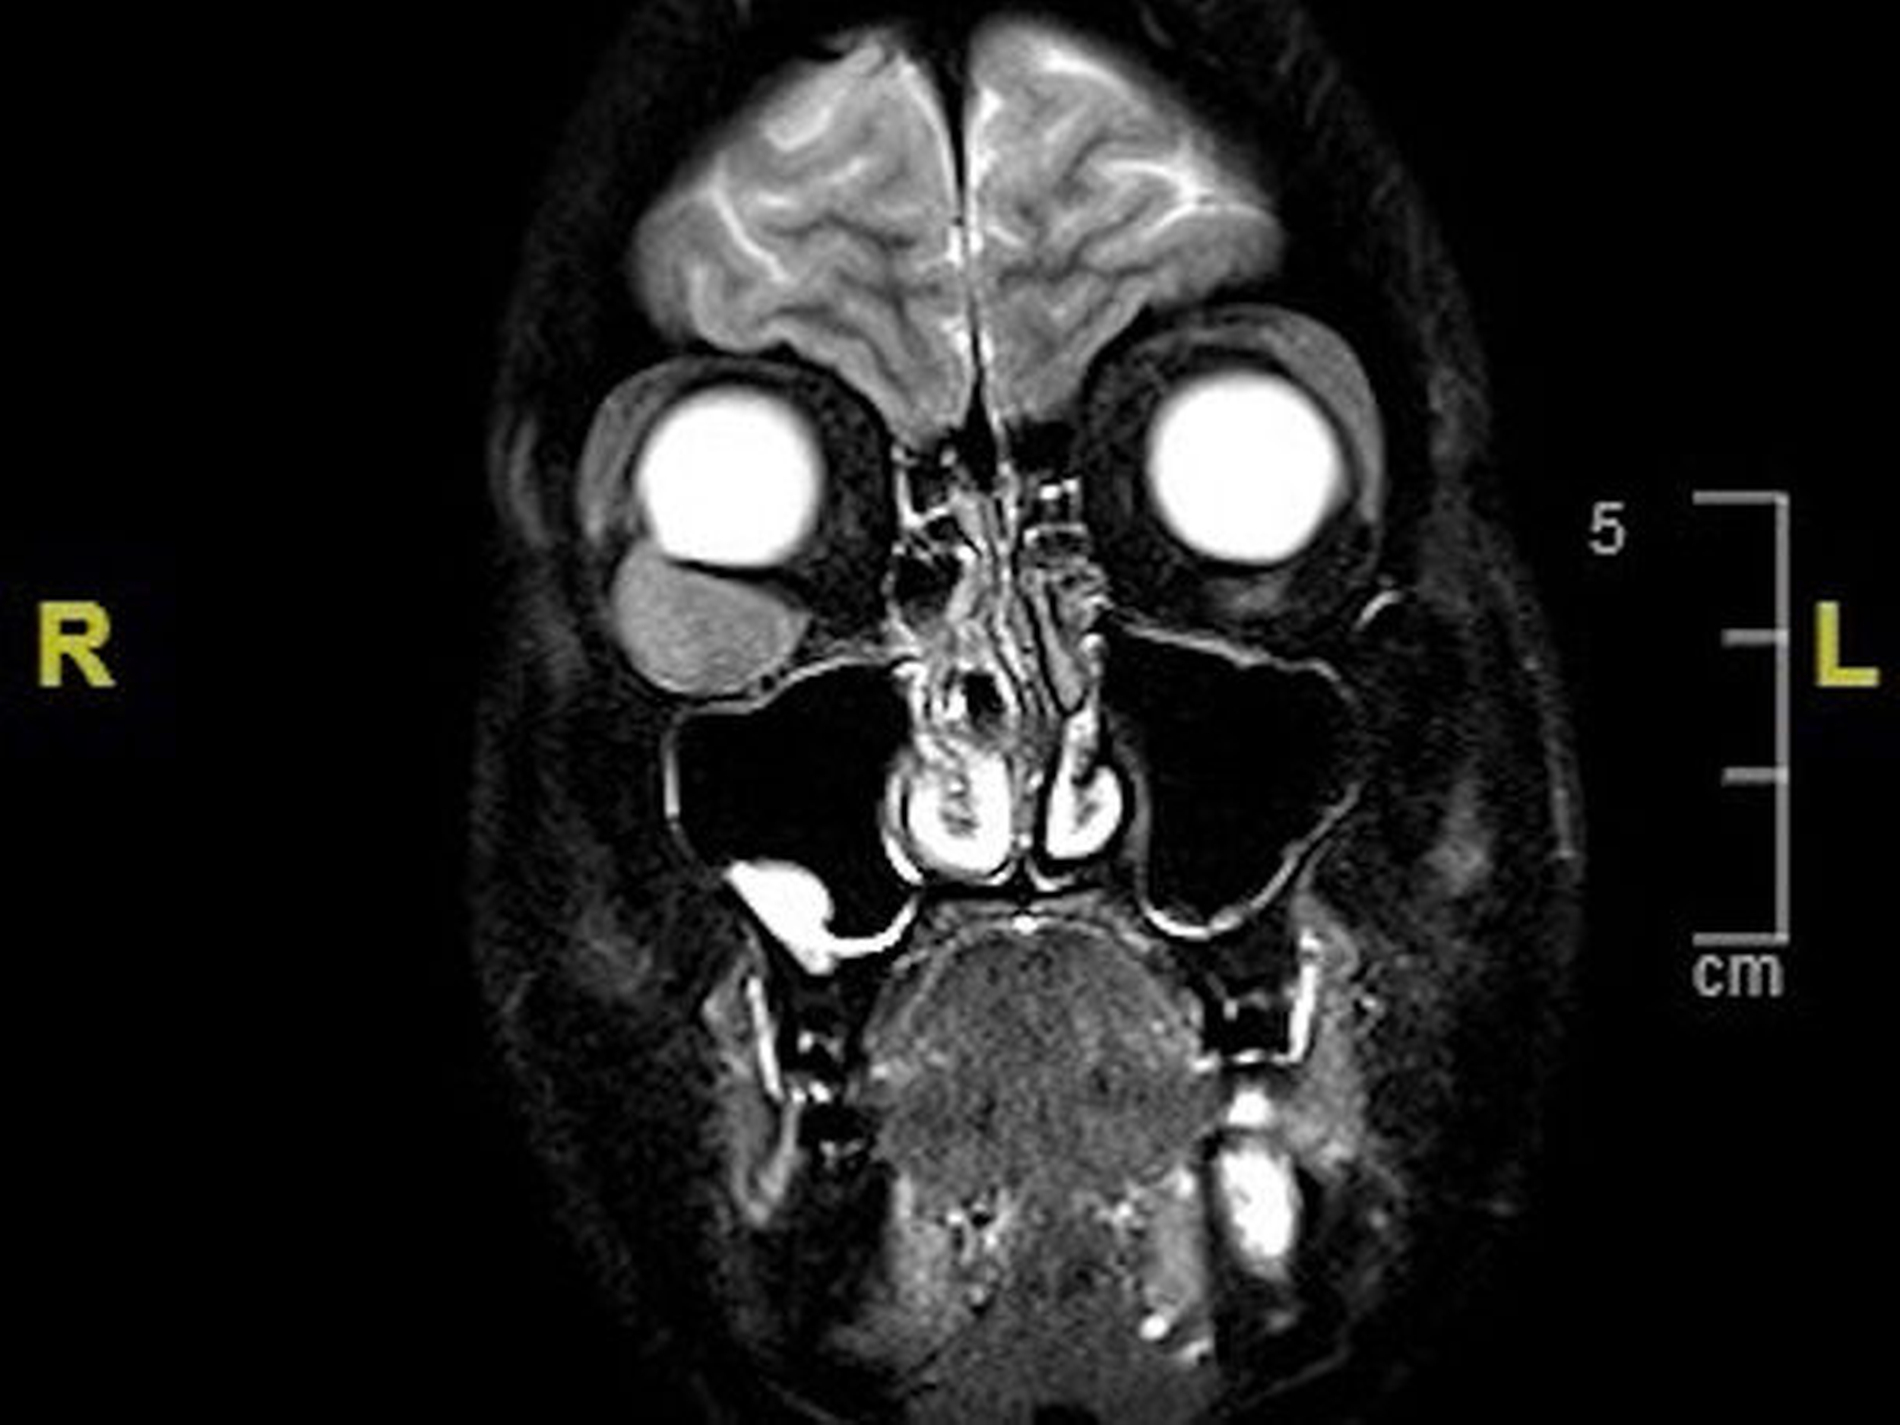

Zur Kontrolle erfolgten MRT-Kontrollaufnahmen des ganzen Körpers in einem dreimonatigen Abstand. Bei Vorstellung in unserer Klinik zeigte sich abgesehen von einem diskreten Bulbushochstand und Exophthalmus rechts ein unauffälliger klinischer Befund. Im MRT zeigte sich eine intraorbitale Raumforderung (Abbildung 1). Die histologische Untersuchung bestätigte den Verdacht auf eine Neumanifestation des Leiomyosarkoms (Abbildungen 2, 3).